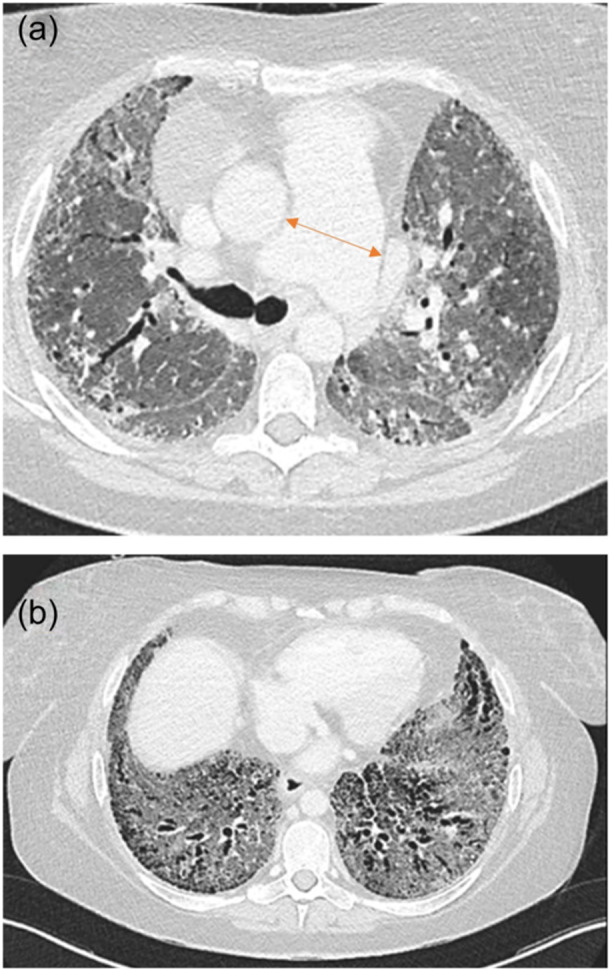

Pulmonary hypertension (PH) is a frequent complication of chronic lung disease (CLD). However, PH is difficult to diagnose early since accompanying symptoms overlap and are similar to those of the underlying CLD. In most cases the PH is mild to moderate and therefore physical signs may be absent or subtle. This consensus paper provides insight into the clues that might suggest the presence of occult PH in patients with CLD. An overview of current diagnostic tools and emerging diagnostic technologies is provided as well as guidance for the work-up and diagnosis of PH in patients with CLD.